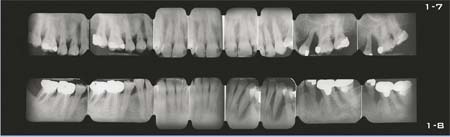

Nun liegen wichtige klinische Befunde vor: Röntgenstatus (mindestens 16 Bilder) (Abb. 1-10 bis 1-14 und 1-18), Panoramaaufnahmen (Abb. 1-15 bis 1-17), Parodontalstatus (Abb. 1-9) und vor allem Information über die Fähigkeiten und den Willen des Patienten zu einer effektiven Plaquekontrolle (Abb. 1-19 bis 1-24).

Abb. 1-7 und 1-8 Der aus 16 Aufnahmen bestehende Röntgenstatus weist eine schwere, generalisierte Parodontalerkrankung mit einigen besonders gefährdeten Stellen auf.